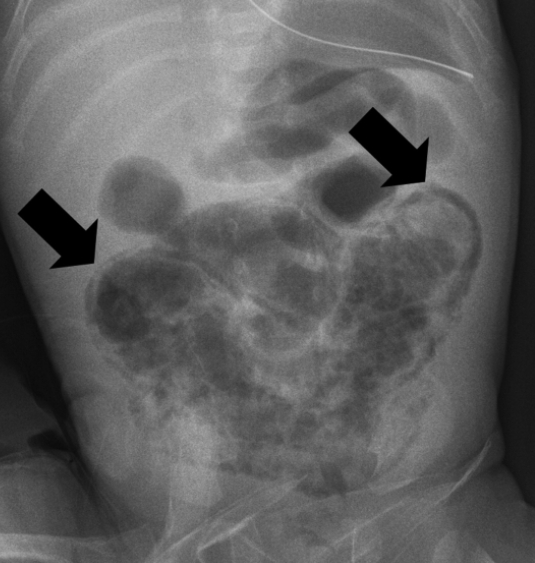

Necrotizing enterocolitis

path: dead gut

demographics: premature, in NICU for other problems

symptoms: ICU baby start having bloody bowel movement

diagnosis: xray shows air in wall (pneumatosis)

treatment: NPO, TPN, IV antibiotics against bowel anaerobes, surgery

complication: surgery and shortgut syndrome